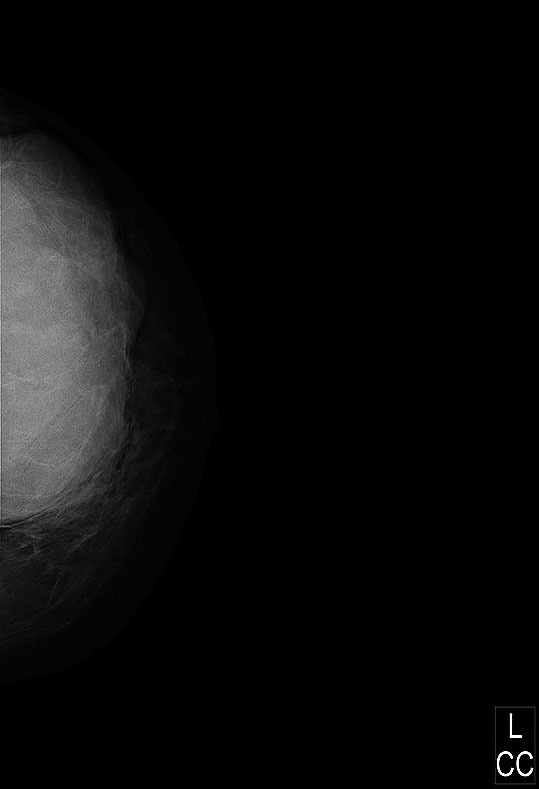

Обратилась повторно в онкоцентр только 17.12.2010 г. при DR–маммографии (рис. 16).

Рис. 16. В левой молочной железе, занимая все квадранты, определяется тень 13 x 10 см, контуры неровные, частично нечеткие. Заключение: опухоль левой молочной железы (О. В. Трусова)